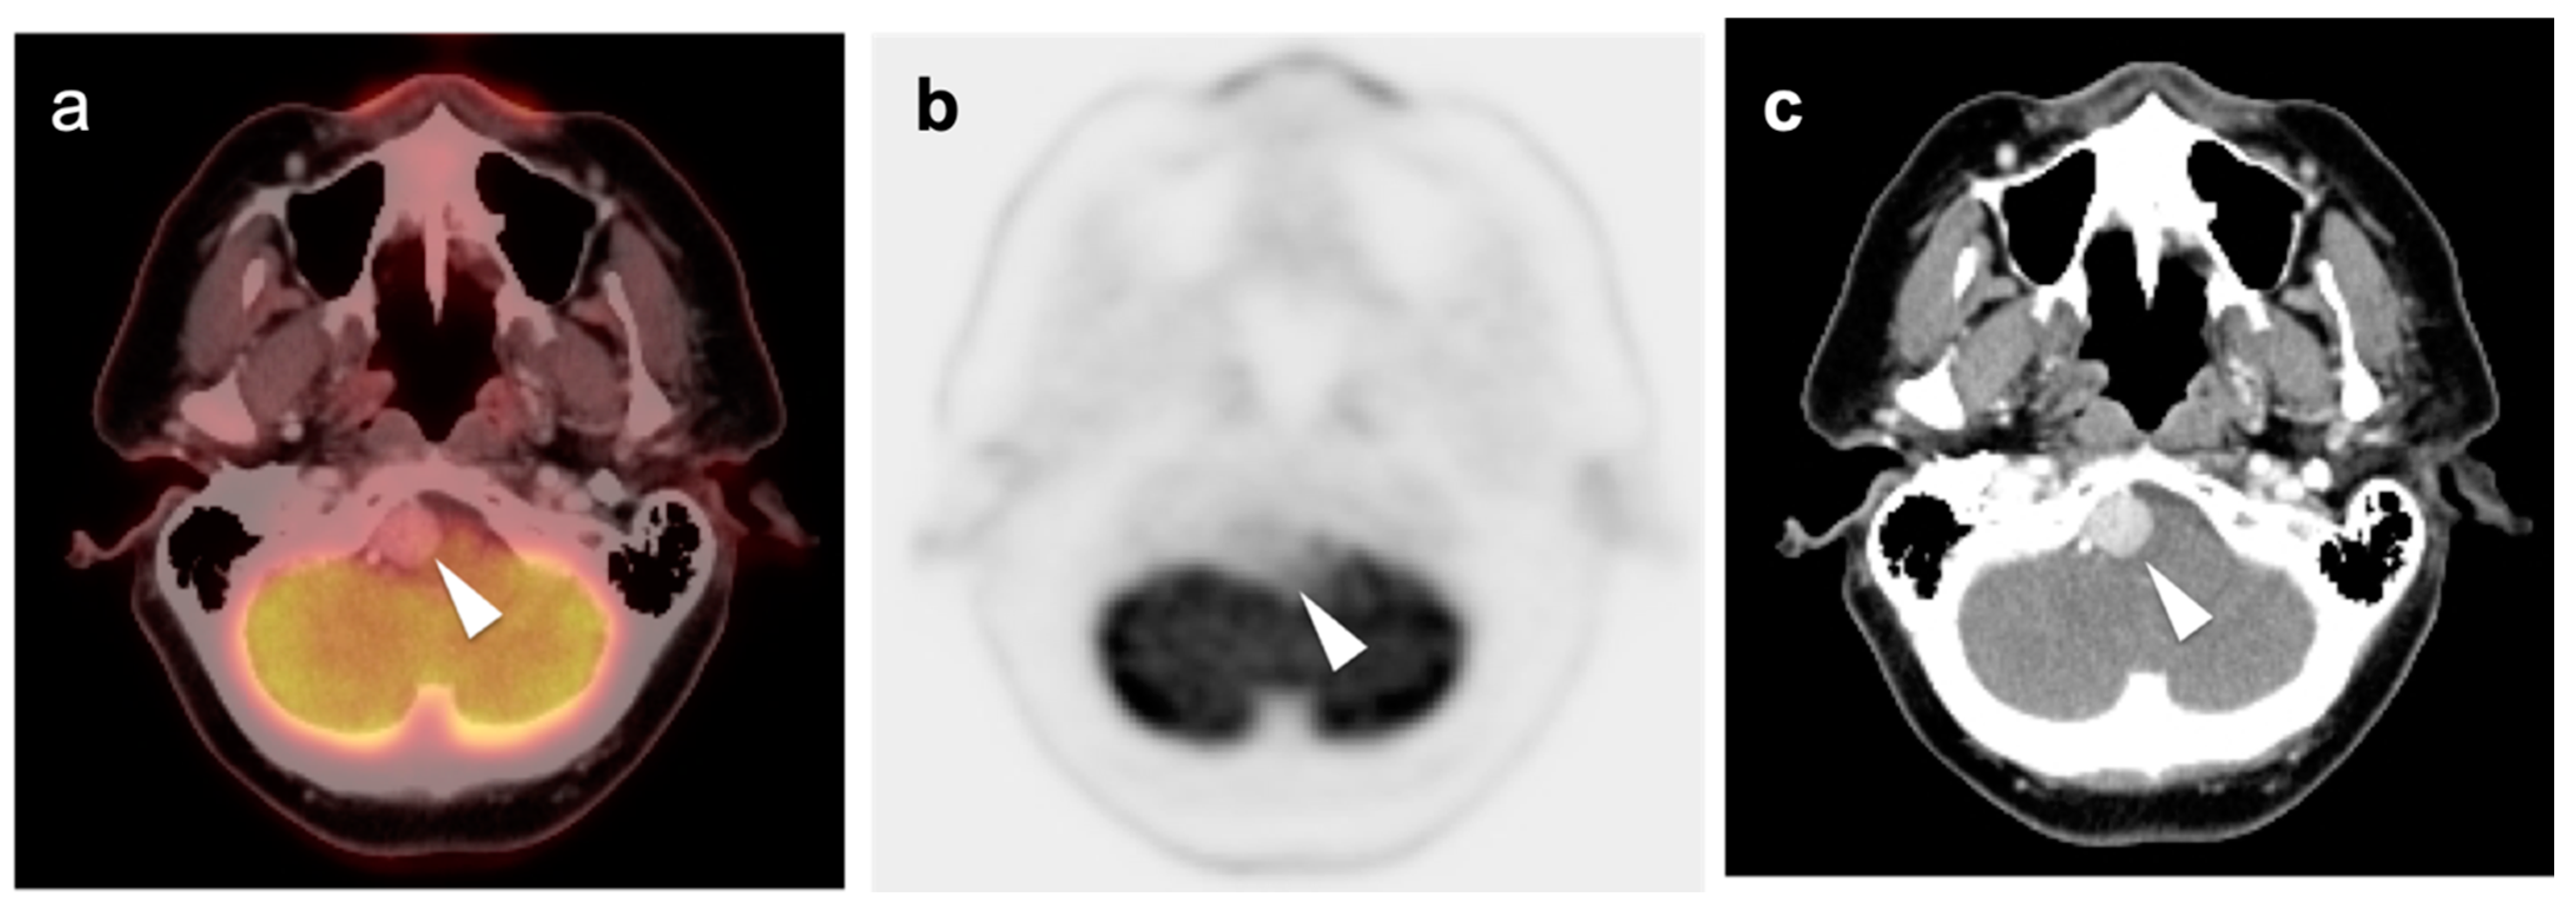

3.2. Paraneoplastic CNS Manifestations and Sources of False Positive FDG PET Scans That Can Mimic Brain Tumors

3.3. Primary Brain Tumors

3.4. CNS Lymphoma